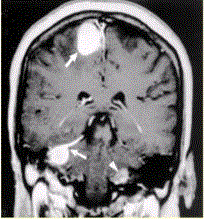

问题 患者男,20岁,头痛、步态不稳。MRI显示如下图。 可能的诊断是

选项 A.神经纤维瘤病Ⅱ型 B.神经纤维瘤病Ⅰ型 C.多发脑膜瘤 D.多发神经鞘瘤 E.多发转移瘤

答案 A